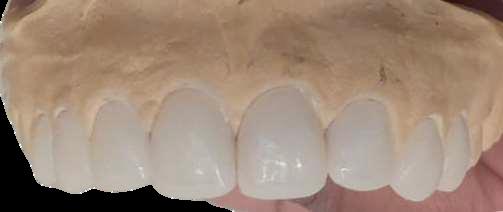

Paciente llega a la consulta por la separación de sus piezas dentales porque no se bien estéticamente y decide realizarse unas carillas dentales de material de disilicato de litio. El material de disilicato de litio es un material compuesto de cerámica de alta resistencia y estética, compuesto de vidrio y cristales de litio sus propiedades incluyen gran durabilidad, y un aspecto natural y buena incompatibilidad que lo convierten en la mejor opción para la restauración

(FIGURA 1)

En la (figura 1) se observa el escaneado de los modelos de yeso que se le tomaron al paciente para diseñar las carillas dentales

En la (figura 2) se observa el escaneado de los modelos de yeso y en la imagen se observa la oclusión de los modelos así para poder diseñar las carillas dentales

En la (figura 3) se observa el modelo de yeso con las futuras carillas posicionadas revisando los parámetros para diseñar las coronas revisando el eje de inserción.

En la (figura 5 y 6) se observa las carillas de disilicato de litio ya talladas en el inLab MC X5

(FIGURA 2)

(FIGURA 3)

(FIGURA 5)

(FIGURA 4)

(FIGURA 6)